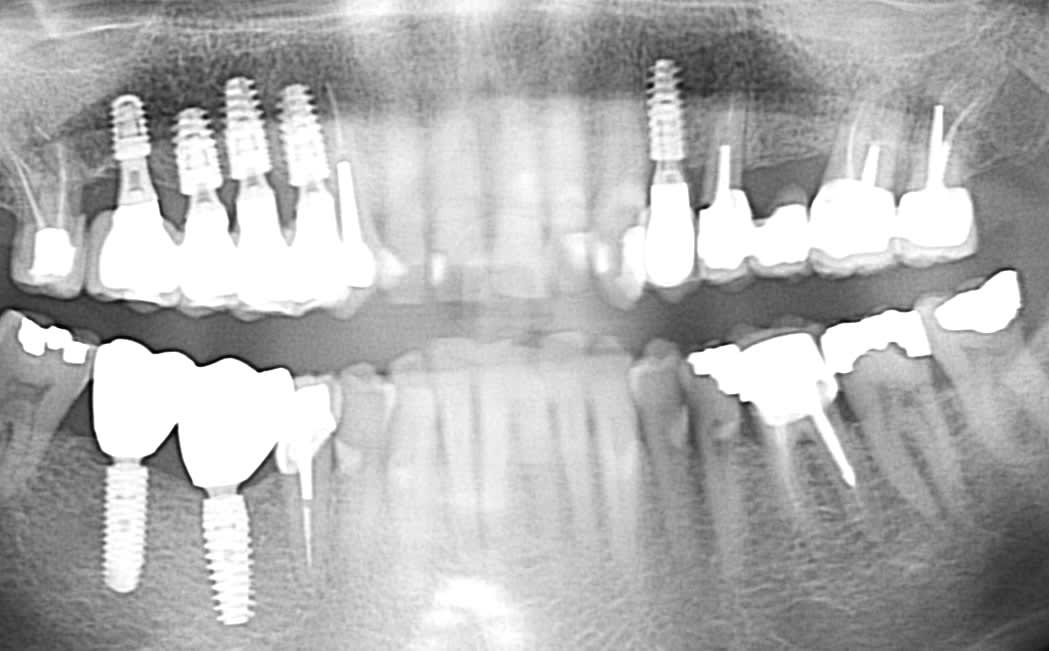

Les éléments de 14 à 17 sont solidarisés et naturellement , la céramique a fracturé sur 15 . J'ai donc coupé en mésial et distal pour reprendre L'empreinte pensant pouvoir dévisser le pilier.

Aucun de mes embouts fonctionne ( Astra, Anthogyr, Nobel..) donc avez-vous une idée de la marque ? ( Ankylos ? )

J'ai l'impression que ce sont des AXIOM

En bas oui, un reg et un PX….mais pour le haut le col semble différent….donc rétro pour ne pas dire de bêtises

En haut c’est plus un implant genre interactive ID, ou Keystone genesis, etc….ou même genre quatro blue skybio….mais la pano ne me donne pas assez de détails pour sortir une identification fiable

Ci-joint la rétro. En effet, j'ai bien posé des Anthogyr en bas. On distingue les découpes . Si non identifié : je retaille et empreinte conjointe classique mais à regret.